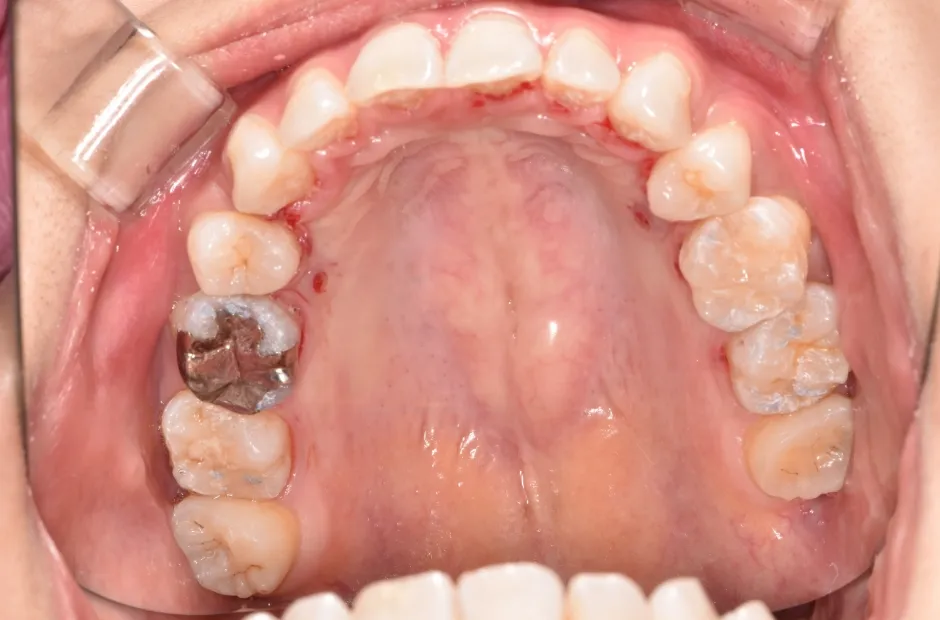

治療前

叢生

| 診断名・主訴 | 叢生 |

|---|---|

| 年齢・性別 | 43歳・女性 |

| 治療期間・回数 | 2年7か月 27回 |

| 治療に用いた主な装置 | 舌側矯正 |

| 抜歯部位 | 両顎4,4 |

| 治療費 | 100万円(税抜) |

| リスク・副作用 | 装置による違和感・疼痛・歯肉退縮・歯根吸収・虫歯のリスクなど |